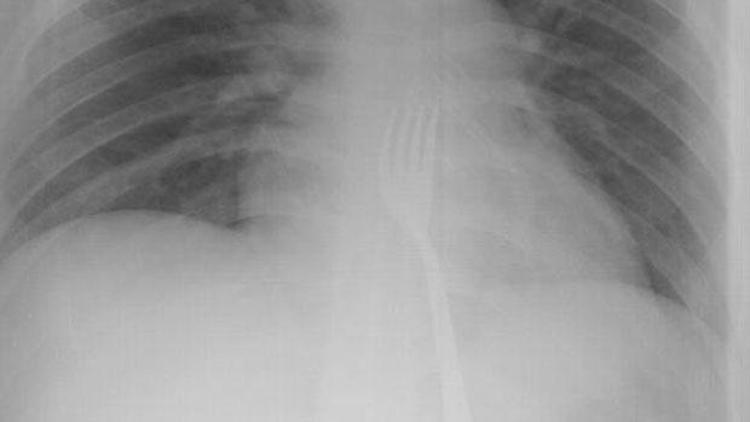

Çeşitli sağlık problemleri olduğu belirtilen 20 yaşındaki O.A'nın çatal yuttuğunu fark eden ailesi, oğullarını Necmettin Erbakan Üniversitesi (NEÜ) Meram Tıp Fakültesi Hastanesine götürdü. Çekilen röntgen filmlerinde, çatalın midede olduğu görüldü. O.A'nın midesinden 15 santimetrelik metal çatal, başarılı operasyonla çıkarıldı. O.A, taburcu edildi.

Hastanenin Genel Cerrahi Anabilim Dalı Öğretim Üyesi Prof. Dr. Mehmet Erikoğlu, yaptığı açıklamada, O.A'nın acil servise başvurarak, çatal yuttuğunu söylediğini anlattı. Kontrollerde çatalın yemek borusunun sonuna kadar inip midede kaldığını gördüklerini aktaran Erikoğlu, büyük olması nedeniyle çatalı operasyonla mideden küçük kesiyle çıkardıklarını ifade etti. Küçük bazı yabancı cisimlerin mideden atılabildiğini anlatan Erikoğlu, "Yabancı cisim düz yutulmuş olsaydı, ciddi sıkıntılar doğabilirdi. Çatal tersten yutulduğu için vücuda bir zararı olmamış. Bugüne kadar çatal yutmasıyla ilk kez karşılaştık." diye konuştu. Erikoğlu, yabancı cisimlerin vücuda vereceği zararın büyük olabileceğini, ailelerin özellikle bu konularda dikkat etmesi gerektiği uyarısında bulundu.